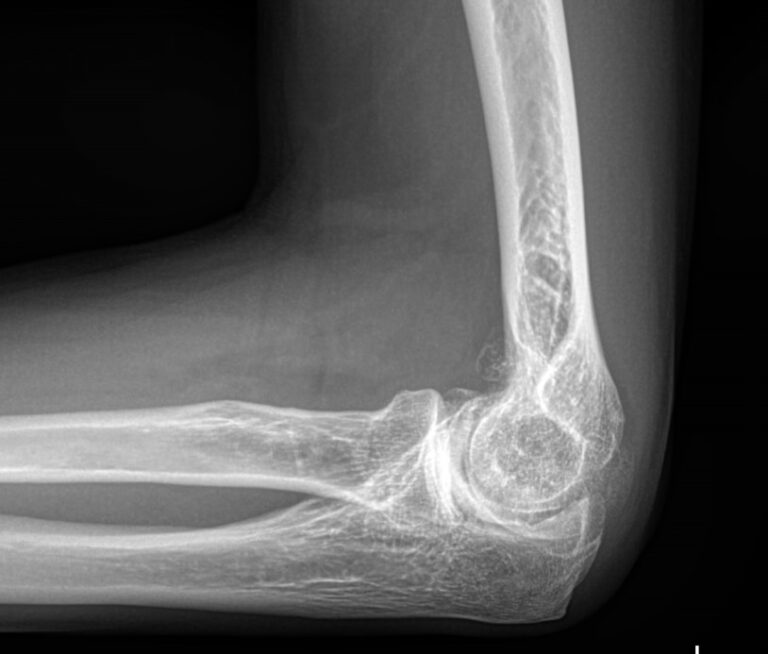

Локтевой сустав считается сложным, он состоит из 3 костей, плечевой, локтевой и лучевой, образующих, соответственно, 3 сустава. Такое строение позволяет свободно двигать рукой и поворачивать ее, обеспечивая достаточный для человека объем движений. Патологии сустава серьезно ухудшают двигательную активность и вызывают болезненные ощущения.

При обращении с типичными жалобами на локтевой сустав врач ― ортопед, травматолог или онколог ― назначает рентгенографию в качестве первичной диагностики. Обычно, этого бывает достаточно для постановки диагноза и выбора метода лечения. В более сложных или запущенных случаях всегда можно дополнить исследование МРТ, КТ или УЗИ.

Что покажет рентген локтевого сустава

• Отек мягких тканей;

• Конгруэнтность и состояние суставных поверхностей, например, наличие эрозии и уплотнение суставных поверхностей, а также костные разрастания

• Состояние суставной щели ― сужение, выпот, обызвествление капсулы;

• Структура костной ткани ― типичная, деструкция или участки повышенной плотности и вздутия, остеопения, иные патологии;

• Травмы ― переломы;